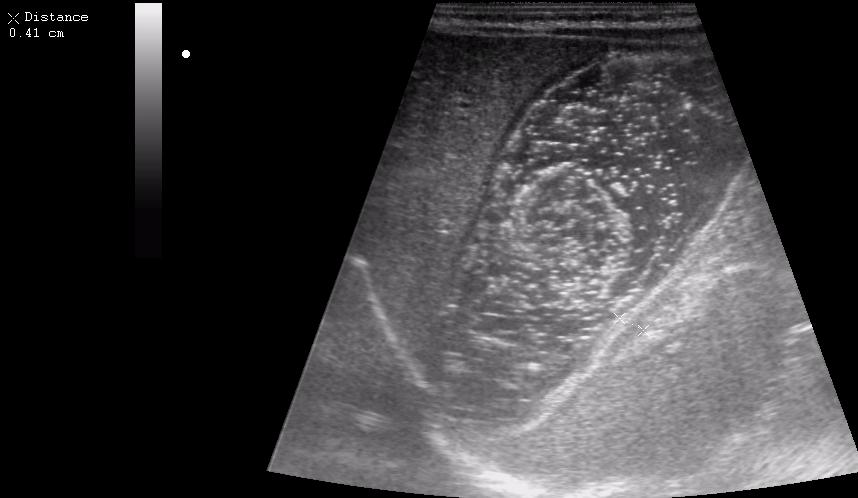

Ребёнок 1 месяц 10 дней от родy, с отсуствием прибавки в весе.

Hypertrophic pyloric stenosis.

Criteria:

1.Pyloric channel > 12 mm in length

2.Muscular layer thickness > 3-4 mm

3.Donuts sign at transverse scanning